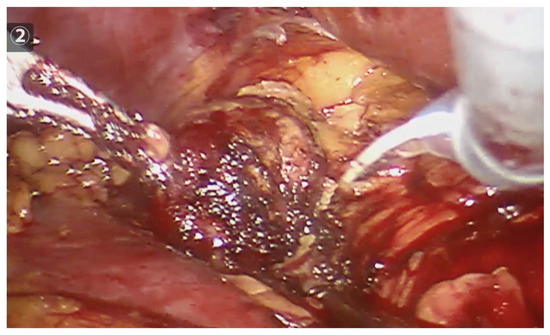

Figure 3.

Robotic tumor resection, after completing the peritumoral radiofrequency, clearly shows a necrotic halo, which will guide the resection.